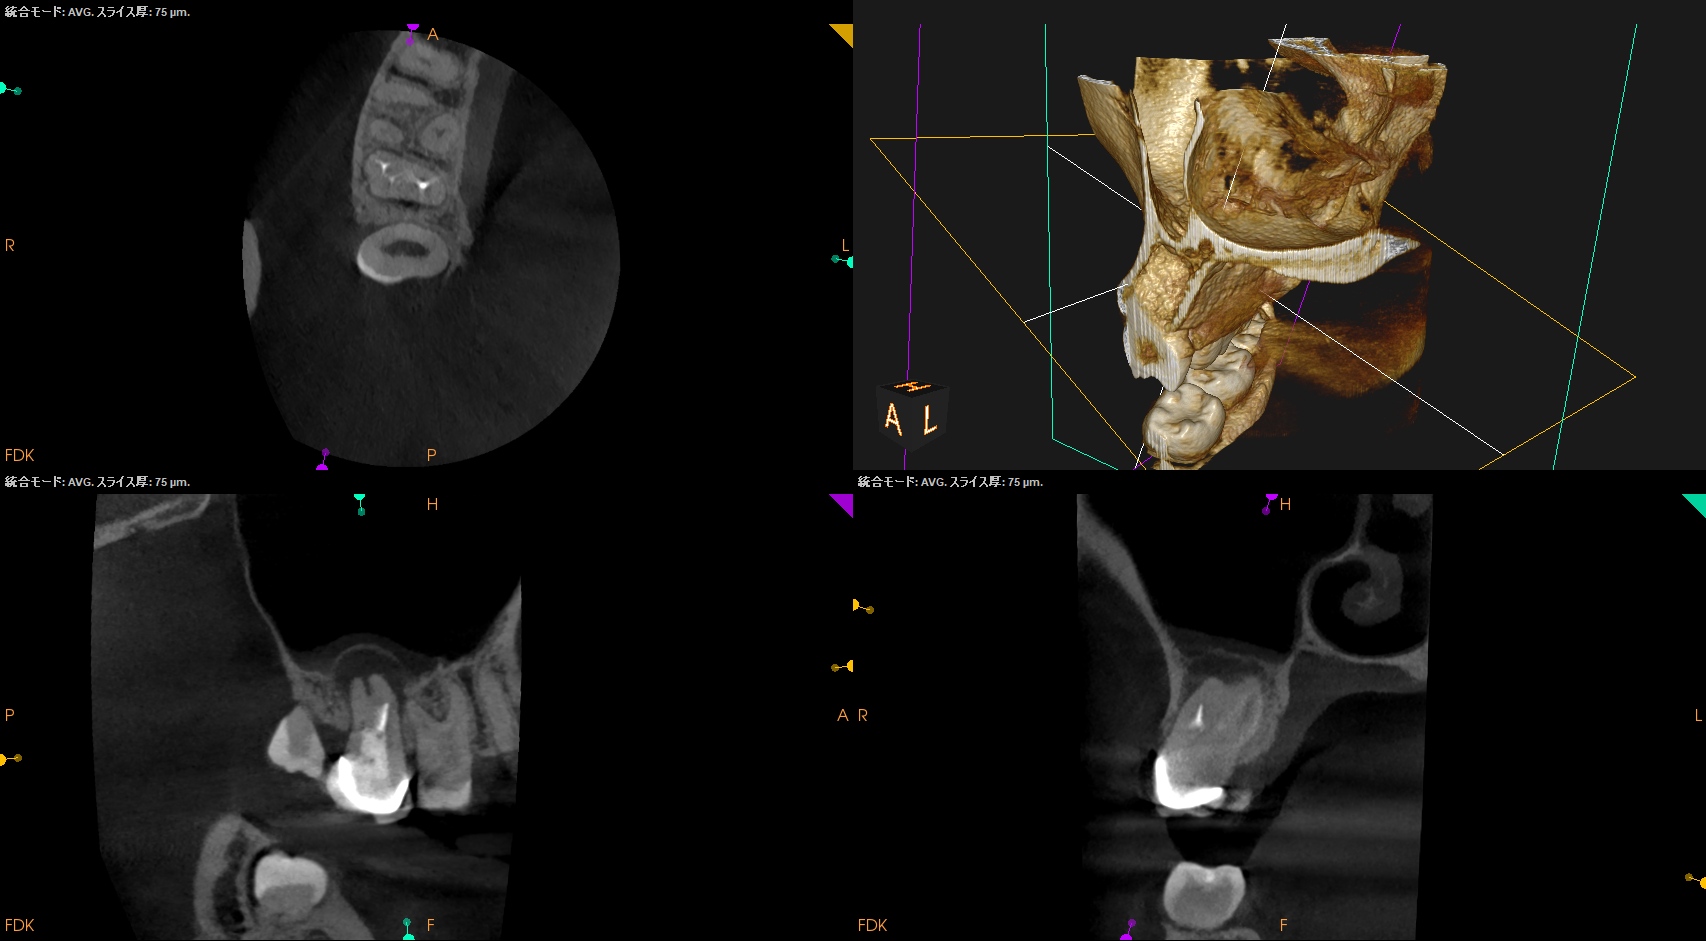

術後にPA, CBCTを撮影した。

MB

DB

P

B